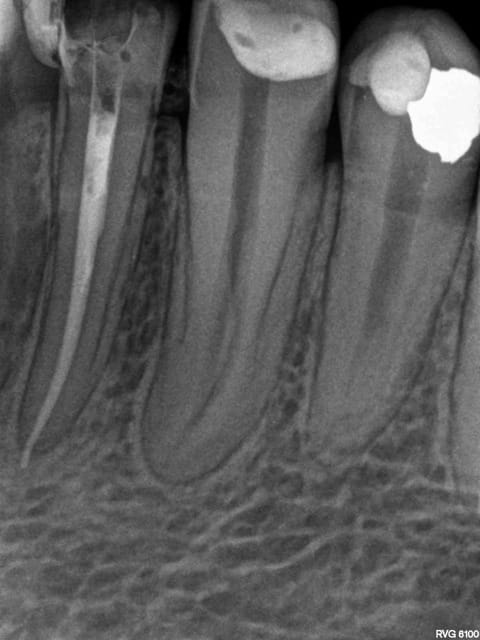

> > > Je ne vois pas où est l'aléa thérapeutique dans ce grand n'importe quoi !

> > Pulpo

> > > pour parodontite apicale aigue, pas de digue, pas d'angulateur, butée......

> > > Il nique la dent de ce pauvre patient par manque de compétence et vient

> ton obturation en mésial ne va pas à l'apex!

A l'apex radiologique c'est sur. Compter 0,5 à 1 mm en moins pour l'apex physiologique.

> > ton obturation en mésial ne va pas à l'apex!

> A l'apex radiologique c'est sur. Compter 0,5 à 1 mm en moins pour l'apex

> physiologique.

Ah d'accord donc tu as un dépassement sur la racine distale?

On n'a pas parlé de la distale mais c'est vrai que pour moi c'est nettement plus chiant à reprendre que la mésiale. Pour enlever toute cette substance radioopaque il faut beaucoup aléser, et il en restera toujours.

Oui -)))) postes un peu des radios de tes endos micro métrées pour voir.

La radio cone en place était un peu plus sexy. Mais ca ce sont les aléas du système B. Pour 80 boules je ne me fais pas chier à tout reprendre. ( canaux mésiaux en y tu noteras)